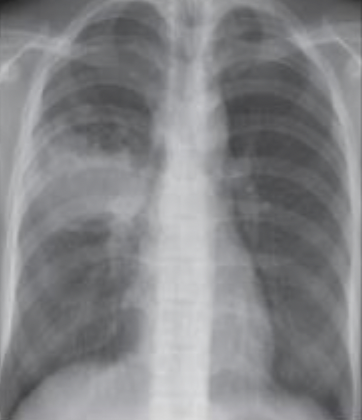

Q

What is this ?

A

Primary TB

-Primary lung lesion (Ghon focus)

-Associated lymph node enlargement

lung focus + lymph nodes = Ghon complex